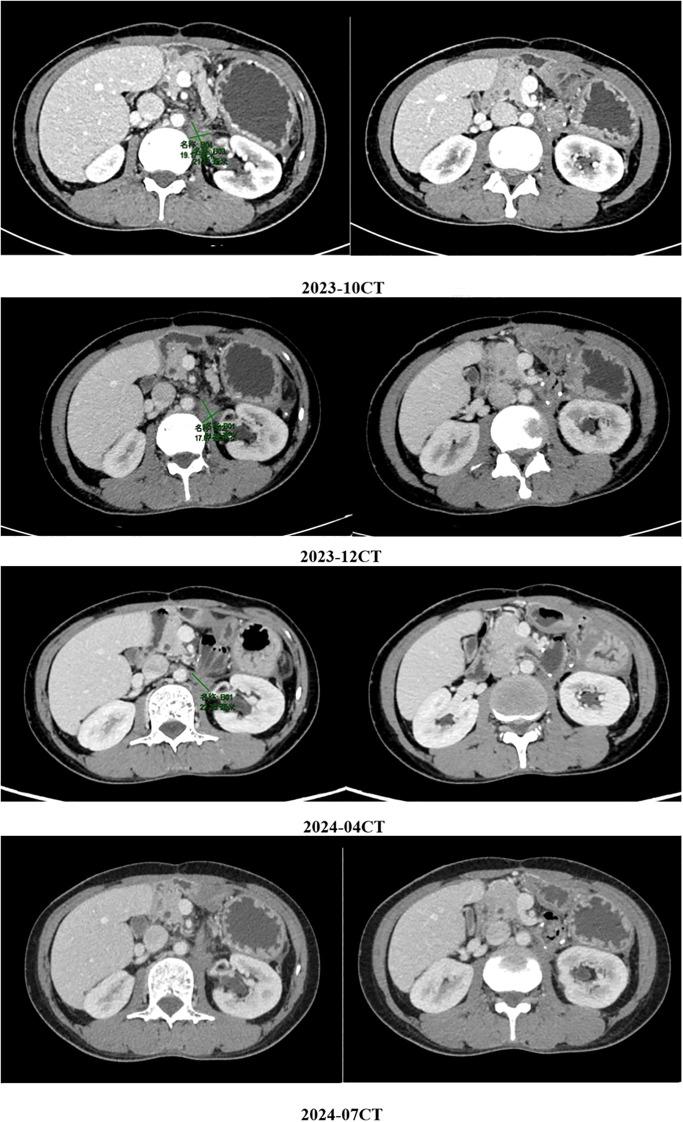

This study reports a 40-year-old male with small intestinal stromal tumor (SIST). After initial surgery and adjuvant imatinib, the tumor recurred. The patient then received multiple rounds of treatment with targeted drugs and surgical interventions. Through comprehensive analysis of gene mutation profiles (KIT and HRR gene mutations, including BRCA2), a combination therapy of fluzoparib, pamiparib, and ripretinib was administered, stabilizing the patient's condition with significant efficacy. This case highlights the importance of genetic testing and personalized targeted treatment strategies for gastrointestinal stromal tumor (GIST) patients.

摘要

本研究报告了一名40岁患有小肠间质瘤(SIST)的男性。在初次手术及辅助使用伊马替尼后,肿瘤复发。该患者随后接受了多轮靶向药物治疗及手术干预。通过对基因突变谱(KIT和HRR基因突变,包括BRCA2)的综合分析,给予氟唑帕利、帕米帕利和瑞派替尼联合治疗,显著稳定了患者病情,疗效显著。该病例突出了基因检测及针对胃肠间质瘤(GIST)患者的个性化靶向治疗策略的重要性。